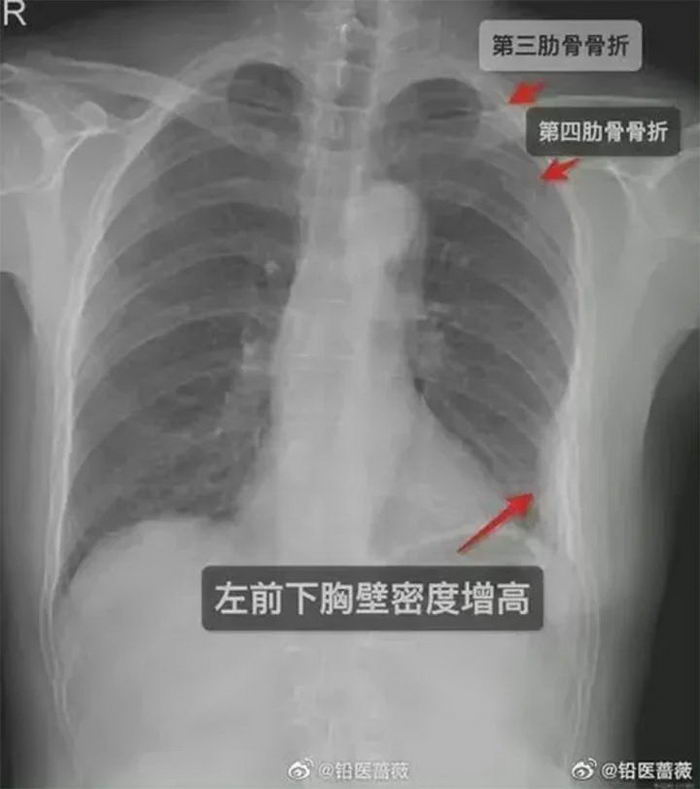

ទោះជាយ៉ាងណាក៏ដោយ ប្រាំថ្ងៃក្រោយមក ការឈឺចាប់នៅក្នុងទ្រូងកាន់តែខ្លាំងឡើង ដូច្នេះហើយ ទើបនាងសម្រេចចិត្តទៅមន្ទីរពេទ្យ ជាលទ្ធផលក្រោយពីការថតកាំរស្មីអ៊ិច គេបានរកឃើញថា នាងមានការបាក់ឆ្អឹង៣ចំណុច ដែល២កន្លែងនៅឆ្អឹងជំនីខាងស្តាំ ចំណុចមួយទៀតគឺនៅផ្នែកខាងឆ្វេងនៃឆ្អឹងជំនី។